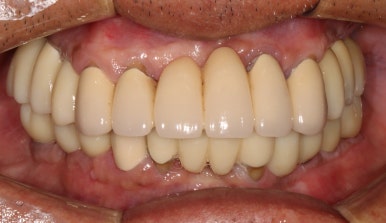

최종보철물을 연결해드리는 오늘,

환자분의 환한 미소가 빛을 발하는 순간입니다.

모든 최종 보철물을 연결하고 나서 치과용 파노라마 사진입니다.

정말 깔끔하게 제작된 것을 보시 수 있을겁니다.

'미적 기준'은 보편적인 측면이 있습니다. 뭔가 나란하고 비율이 대칭인 임플란트는, 잘 모르는 사람이 봐도 잘 되었구나~~ 라고 생각하게 만들어주죠 ^^